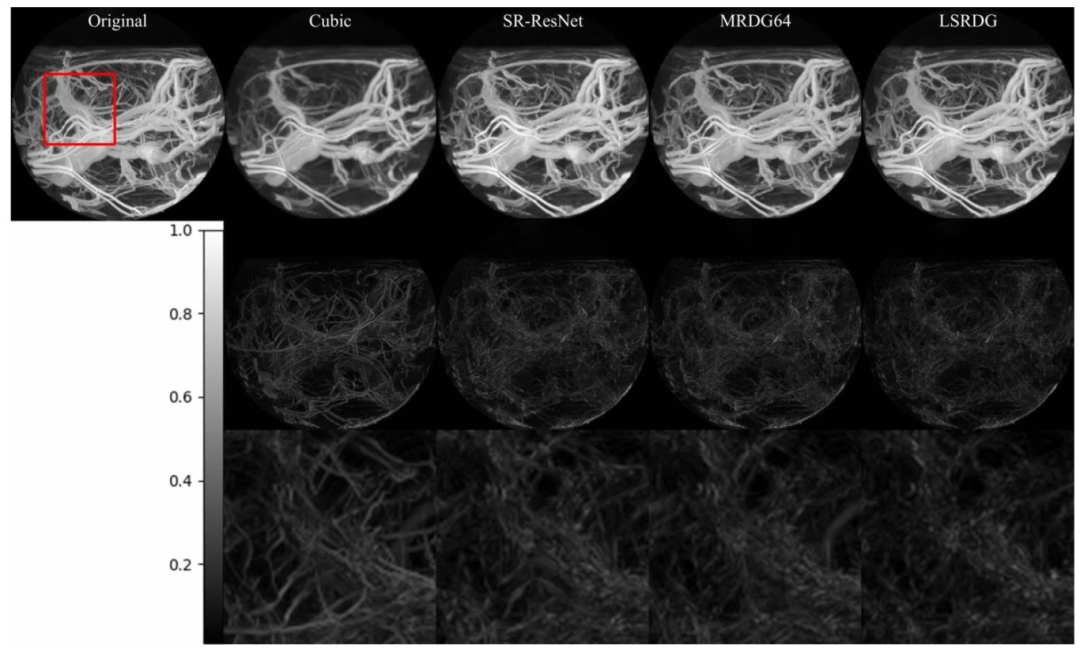

在模型性能方面,LSRDG在健康对照组数据上取得了SSIM 0.983、PSNR 36.80和MSE 0.00021的优异结果,显著优于SR-ResNet(SSIM 0.964、PSNR 34.38)和MRDG64(SSIM 0.978、PSNR 35.47)。对于中风数据,LSRDG同样表现出色(SSIM 0.963、PSNR 34.14),且视觉对比显示,其生成的超分辨率图像更接近真实高分辨率数据,尤其在血管分叉点等细微结构上复原效果突出。

基于HC数据使用PSNR导向训练生成的图像的视觉对比

为使用来自健康对照数据的面向峰值信噪比训练生成的绝对残差图的视觉对比